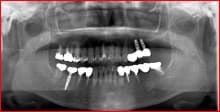

インプラント

インプラント手術用ガイド

インプラント療